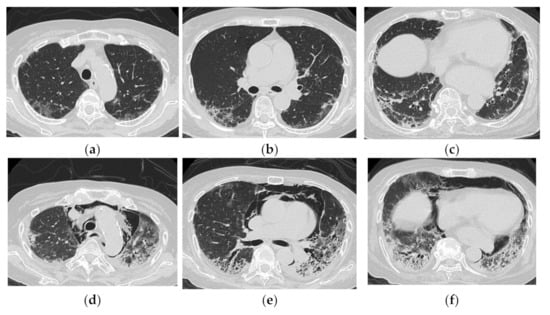

| Predominantly in the lower lobes of both lungs | Diffuse, or diffuse with a predominance of the lower lung zone |

| Peribronchovascular bundle distribution | Peribronchovascular distribution in the lower lobes, with parallel extension to the pleura |

| Reticular shadows and consolidation are common | GGO and consolidation |

| Reduced volume of the lower lobes | Basal volume loss |

| Traction bronchiectasis |

| Distribution along the bronchovascular bundles in the bilateral lower lung fields > diffuse | Diffuse, predominantly in the lower lung fields, or both |

| Reduced volume of the lower lobes | Peribronchovascular lesion of the periphery of lower lobes, with parallel spread to the pleura |

| Reticular shadows or consolidation > GGO | Patchy distribution |

| Good response to treatment but relapses | GGO and consolidation |